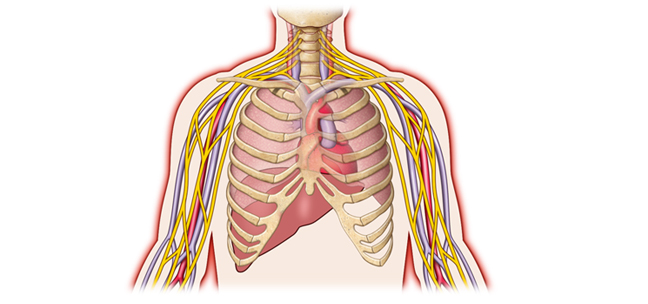

Figure 8: This is an anterior image of the coronal abduction external rotation of the upper extremities sequence in Figure 7. This image displays high signal intensity (white) internal mammary (IM) and hepatic veins (H) reflecting increased thoracic and abdominal pressure secondary to decreased venous return on a T-1 sequence. First fascicle of the serratus anterior muscle (FSA), liver (L), left ventricle (LV), stomach (S). With permission from James D. Collins, MD. Read complete article here.